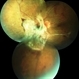

- florid type PDR

- 23-year-old 28-week pregnant female with florid proliferative diabetic retinopathy left eye.